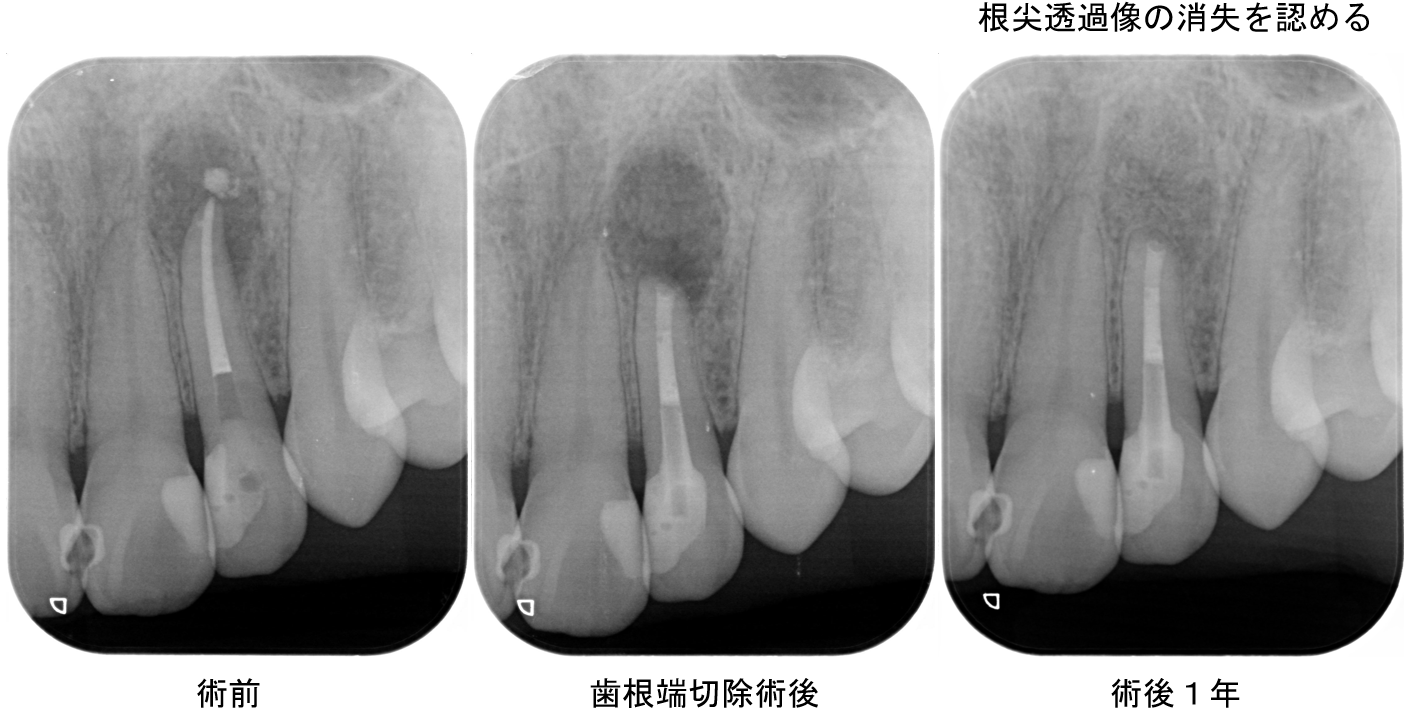

症例3

| 患者様データ | 80代 女性 |

| 来院時の主訴 | 「右上の歯が腫れた。」 |

| 医院の診断 | 慢性根尖性歯周炎 |

| ここがこだわりのポイント!☝ |

患者様はインプラント治療や入れ歯治療に抵抗感が強く、自分の歯で食事をとりたいという希望がありました。MTAを使用した歯根端切除を行うことで、抜歯を回避することができました。 |